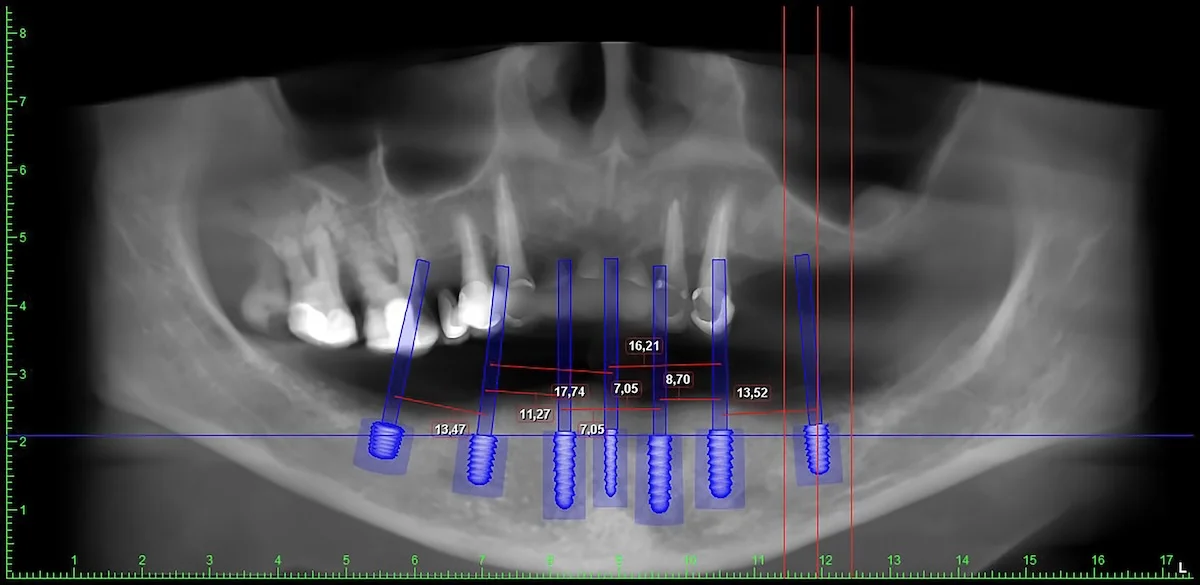

Unsere Praxis ist vollständig digitalisiert und mit einem Oralscanner und 3D-CT ausgestattet. Wir führen Implantatoperationen auf Basis digitaler Planung durch und unsere Kronen werden mithilfe von CAD/CAM-Technologie auf Basis digitaler Abdrücke hergestellt.